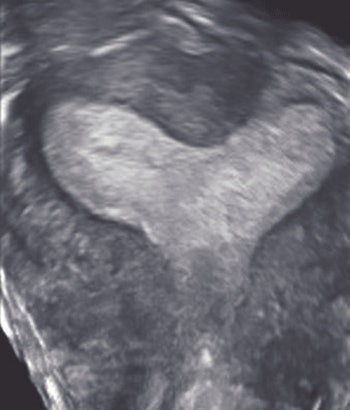

| A 40-year-old woman with a fibroid. Above, transverse view of uterus shows fibroid (calipers). Exact location of fibroid with respect to uterine cavity is unclear because posterior aspect of fibroid obscures side of endometrium. Below, coronal view shows that fibroid is not submucous, but is intramural without distorting shape of uterine cavity. Plane shown here was deemed by radiologist to be best plane to show closest relationship between fibroid and endometrium, showing that the fibroid did not extend into cavity but just abuts it. Benacerraf B, Shipp T, Bromely B, "Which Patients Benefit from a 3D Reconstructed Coronal View of the Uterus Added to Standard Routine 2D Pelvic Sonography?" (AJR 2008; 190:626-629). |